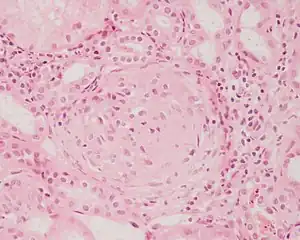

Rapidly progressive glomerulonephritis

Rapidly progressive glomerulonephritis, also known as crescentic GN, is characterised by a rapid, progressive deterioration in kidney function. People with rapidly progressive glomerulonephritis may present with a nephritic syndrome. In management, steroid therapy is sometimes used, although the prognosis remains poor.[9] Three main subtypes are recognised:[4]: 557–558

Histopathologically, the majority of glomeruli present "crescents". Formation of crescents is initiated by passage of fibrin into the Bowman space as a result of increased permeability of glomerular basement membrane. Fibrin stimulates the proliferation of endothelial cells of Bowman capsule, and an influx of monocytes. Rapid growing and fibrosis of crescents compresses the capillary loops and decreases the Bowman space, which leads to kidney failure within weeks or months.